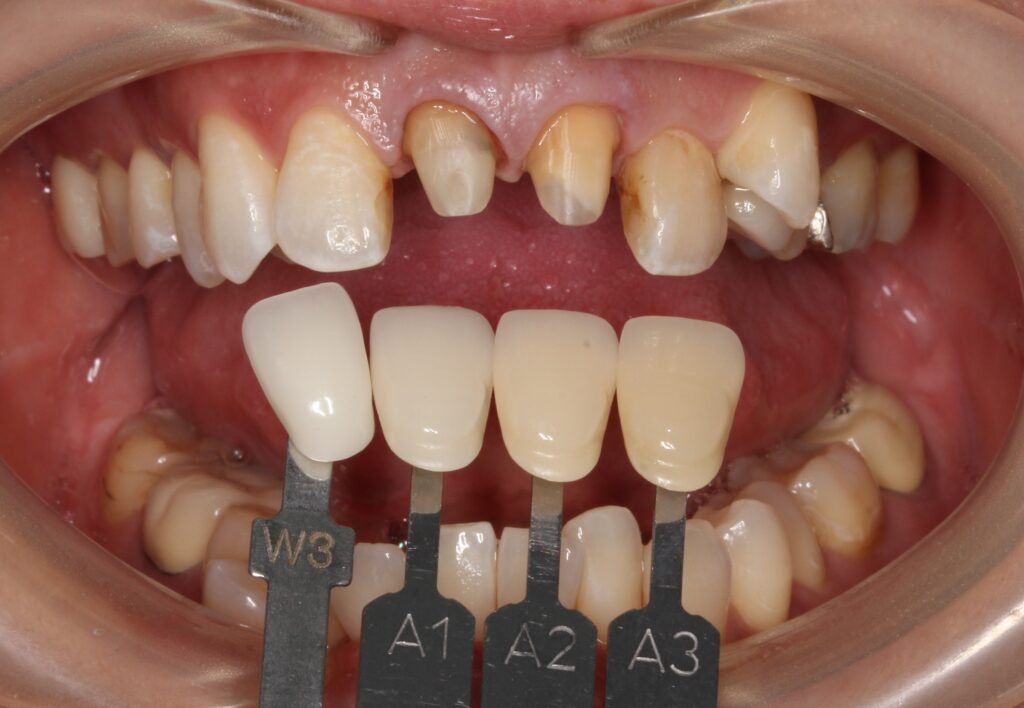

歯の色見本を合わせて、写真で記録しています。

その方によって歯の色は違うために、歯の色見本で歯の色を選んでいきます。

専門の歯科技工士にセラミックを製作してもらい、後日最終的な出来上がったセラミックをセットします。